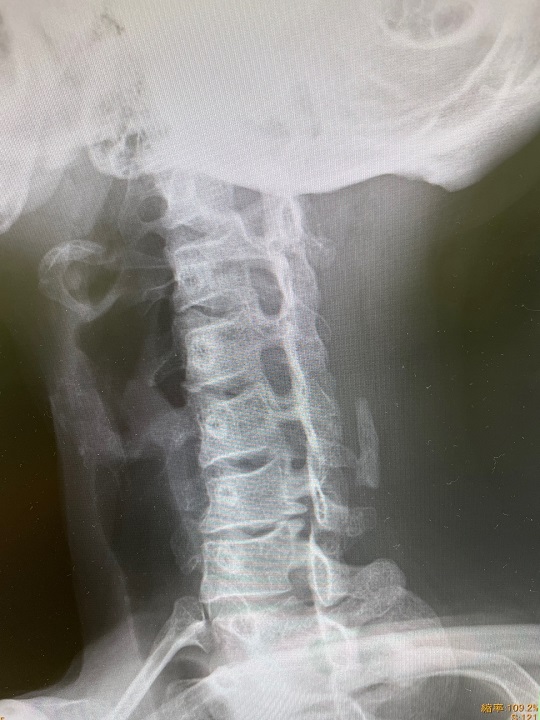

この時から首から腕にかけて調子が下り坂で痛さが徐々にひどくなってきたので撮ってきました、レントゲン。

きれいなストレートネック。

骨の間も狭くなって、神経に触れているのか、姿勢の悪さがここに来て悪さし始めたようです。

ということで3月、滑りはちょっとお休みします。

調子良く滑れていただけに残念ですが、4月、5月滑り行けるように整えます。